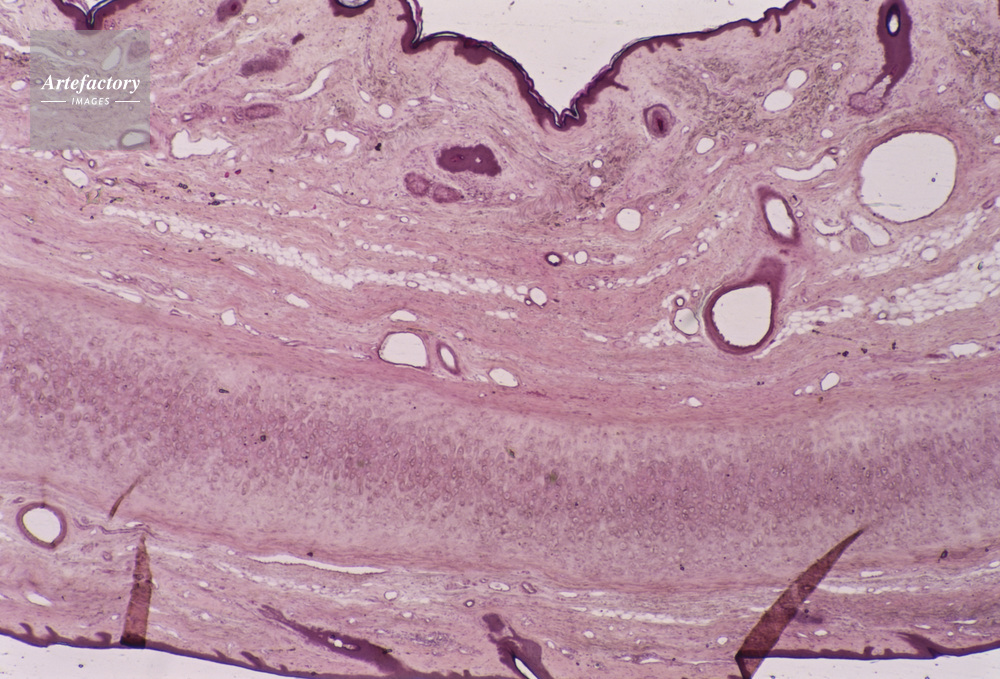

| キャプション | 弾性軟骨,犬,20倍 | 制限事項 | ||

| ソース | ピクセル数 | 5556px × 3773px | ||